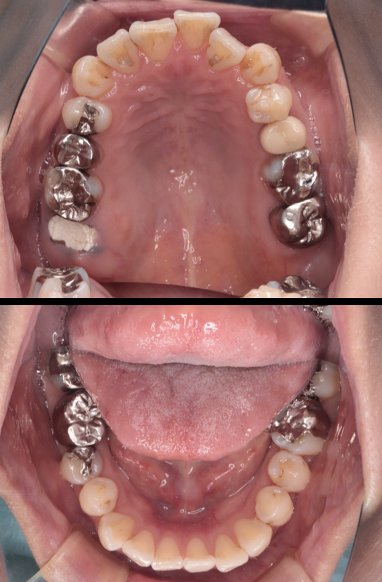

before

after